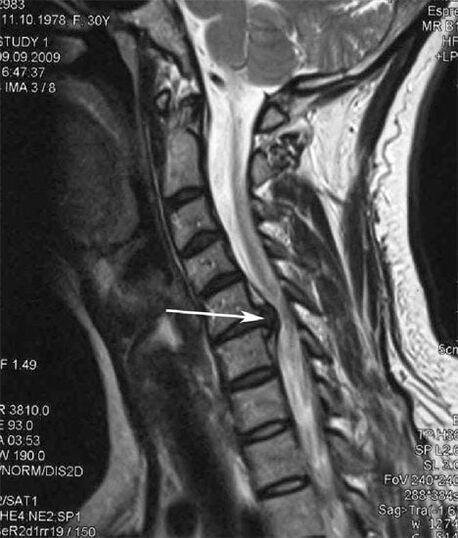

Algstaadiumis tuvastatakse MRI abil osteokondroos. Hiljem saab patoloogiat diagnoosida radiograafia abil. Emakakaela lülisamba röntgenülesvõtetel on märgatav selgroolülide vahelise kauguse vähenemine, patoloogilised muutused tahk liigestes ja osteofütoos.

| Emakakaela osteokondroos | Patoloogiliste muutuste ilmnemine ühes või mitmes selgroo liikumise segmendis. Lülisamba liikuvuse halvenemine, müofastsiaalsete valusündroomide teke ja seljaaju juurte pigistamine | Valu, paresteesia ja motoorsed häired emakakaela piirkonnas, mis levivad pea taha ja ülemistele jäsemetele. Lülisamba iseloomulike muutuste tuvastamine MRT-l ja radiograafial (osteofüüdid, selgroolülide vahekauguse vähenemine, selgroolülide kahjustuse tunnused) |

Paljud inimesed kurdavad, et nad ei saa kaela pöörata tugeva valu tõttu, mis ilmneb pärast järsku raske asja tõstmist. See nähtus näitab herniaalse ketta moodustumist. Selja-, kaela- ja ülajäseme valu põhjus on ühe seljaajust väljuva närvijuure muljumine.